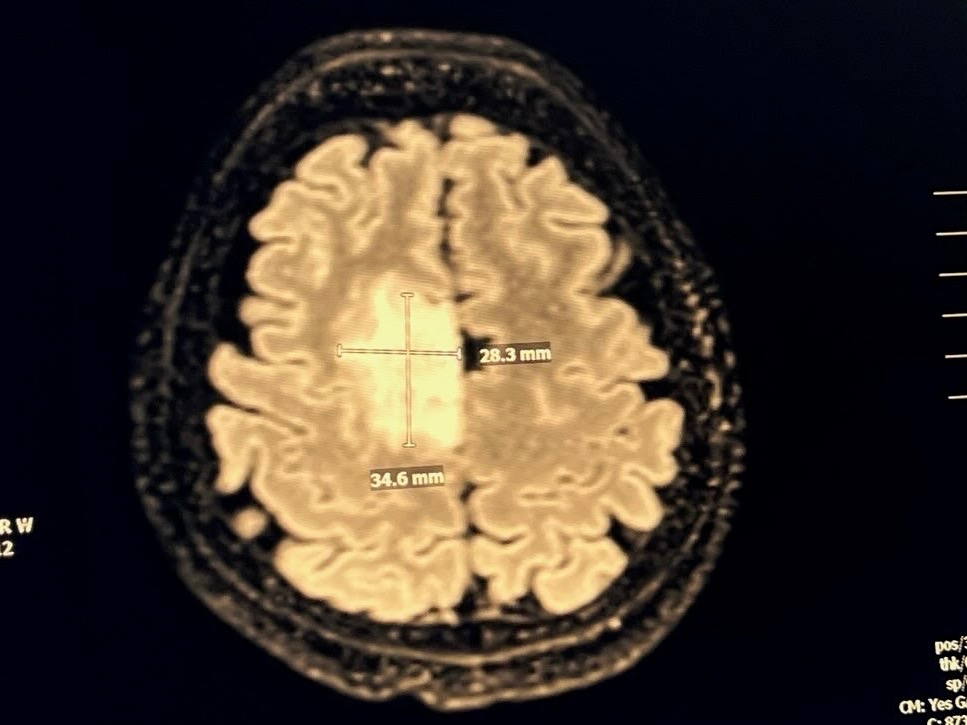

My best friend Jenai had a scary and horrible seizure on Wednesday night. Her brave 12-year-old daughter called 911 and she was rushed to the hospital. Tomorrow she will have brain surgery to remove a large tumor. Jenai doesn’t get benefits or paid sick leave from work. Between medical bills and lost wages, her family will take a big hit. I offered to share this and ask for some help for my dear sweet friend. Her recovery could take months. Even a little bit could help a lot. Thank you!